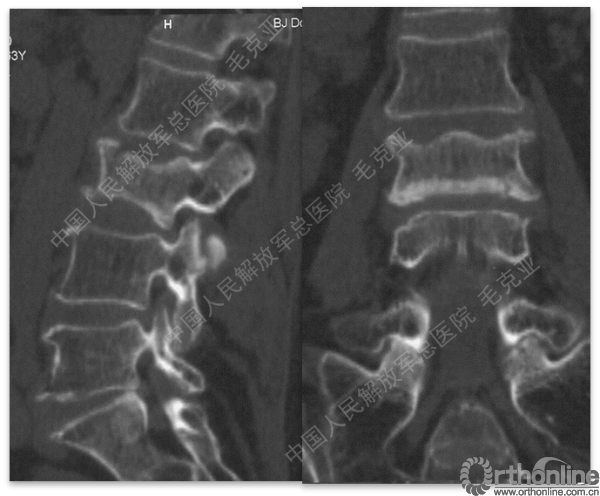

导语:随着社会老龄化的不断加速,骨质疏松性椎体压缩骨折作为一种普遍存在的老年骨科疾病已经成为现今骨科界的一个热点话题。传统的保守疗法治疗效果不佳,而现有的椎体增强技术又具有多种风险和缺陷。针对这种现状,中国人民解放军总医院毛克亚教授提供了一种新的解决方法。